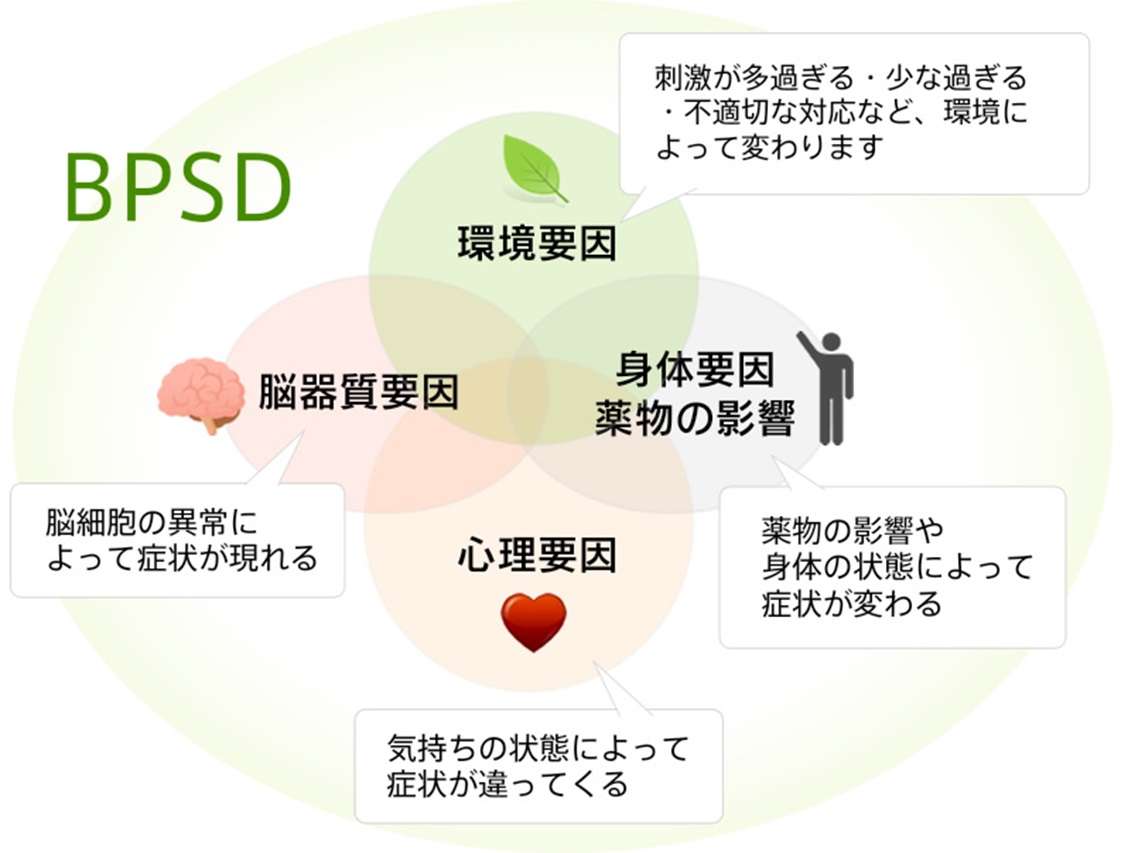

■ 周辺症状(BPSD):環境・心理・身体の要因が関わる“反応としての症状”

周辺症状(BPSD:Behavioral and Psychological Symptoms of Dementia)は、

認知症のある方の日常の中でみられる心理・行動の変化で、

神経細胞そのものの障害だけでは説明しきれない症状です。

国際老年精神医学会は、BPSDを次のように定義しています。

「知覚・思考・気分・行動の異常として現れる、認知症に伴う多様な症状」

つまり、周辺症状(BPSD)とは、

認知症による記憶障害などを背景に、

環境や関わり方、不安や混乱が引き金となって現れる症状ということです。

そのため、同じ認知症であっても、

生活環境や家族との関係性によって現れ方が大きく異なるのが特徴となってきます。

■ BPSDは“本人のSOS”として理解されることが多い

周辺症状は、一見すると「困った行動」に見えますが、

その背景にはさまざまな要因が絡み合っています。

・身体の不調(痛み、便秘、脱水など)

・環境の変化(引っ越し、入院、音や光の刺激)

・不安や恐怖

・薬の影響

・コミュニケーションの行き違い

・生活リズムの乱れ

・孤独やストレス

このように、BPSDは“脳の障害+周囲の環境・関係性”によって生じると考えられています。

そのため、介護の現場では

- 環境調整

- 生活リズムの見直し

- 本人の不快感の軽減

- 関わり方の工夫

によって、症状が大きく改善することも少なくありません。

また、BPSDは“本人の意思”というよりも、

環境にうまく適応できないときの“心と身体の反応”であることも理解しておきたいポイントです。